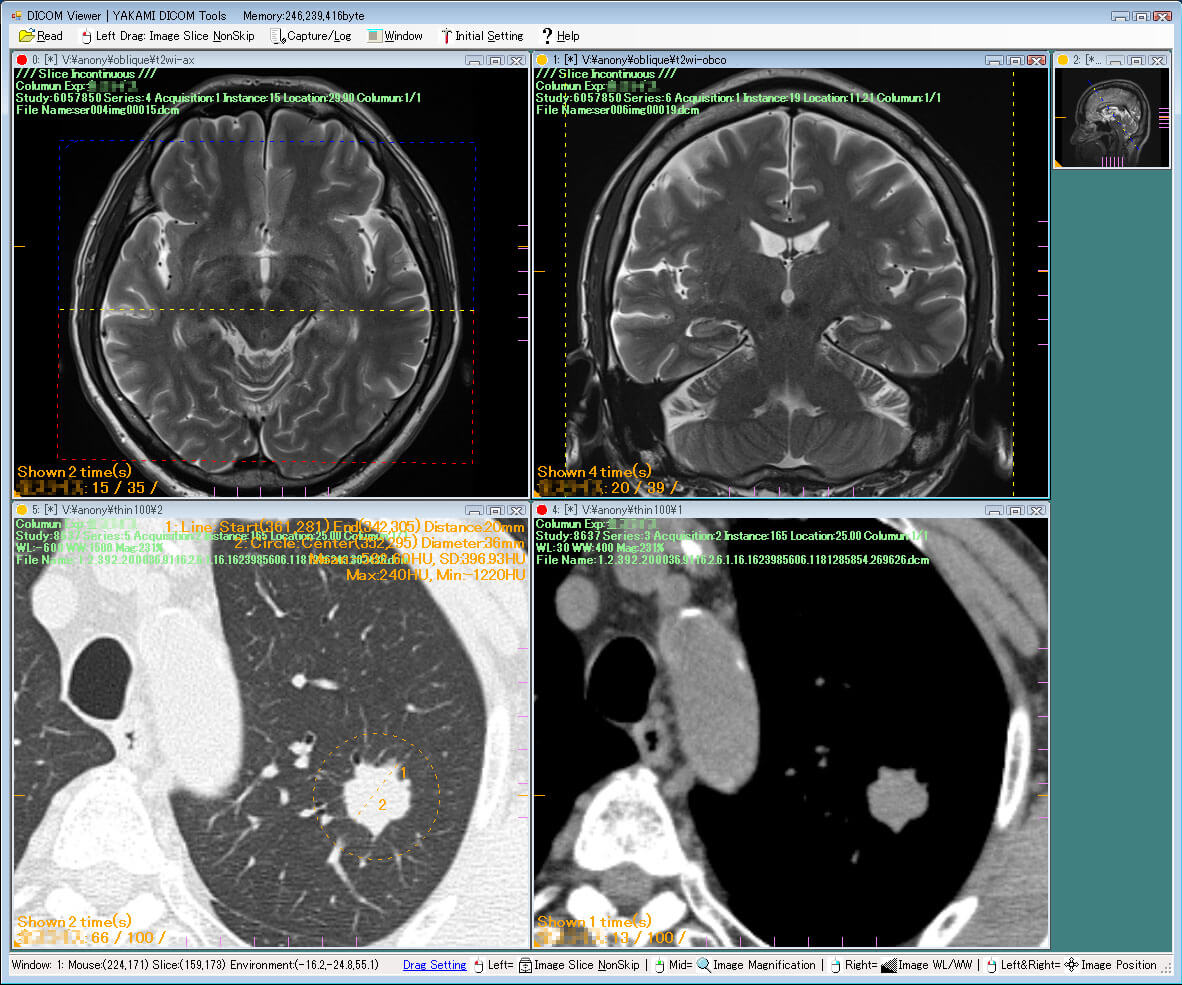

| 25. | Yakami DICOM | Windows | Not available | Y | Y | Y | N.A. | 1 GB | Intel processor/ 2 GB RAM | Free for non-commercial use |